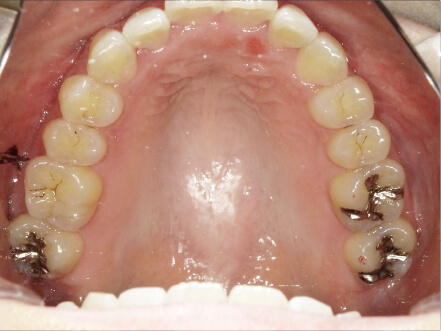

叢生の症例

41歳

女性

正中がズレている。傾いている歯がある。

カウンセリング・診断結果

叢生・アレルギーなし・ext、IPR、アタッチメント、ミニスクリュー、ゴム掛け承諾

治療内容・方法

全額アライナー矯正・左下7セラミックはそのまま進めていく

術後の経過・現在の様子

クリアライナー使用

痛み・歯根吸収・歯肉退縮・虫歯・後戻り

費用・治療期間

880,000円、1年9ヶ月